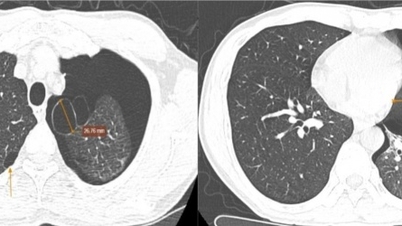

Rumah Sakit Umum Pusat Quang Nam berhasil menangani kasus pneumotoraks kompleks.

Tindakan penyelamatan tepat waktu menyelamatkan seorang pria yang menderita pneumotoraks parah akibat pecahnya kista udara.

Menyelamatkan pasien dengan kista paru-paru pecah dalam kondisi kritis.

Saat sedang makan di sebuah pesta, pria itu tiba-tiba mengalami serangan jantung.

Menyelamatkan pasien dengan pneumotoraks yang menyebabkan sesak napas dan nyeri dada.

Saat bermain dengan kacang hijau, seorang bayi berusia 9 bulan tersedak kacang, yang mengakibatkan pneumotoraks.